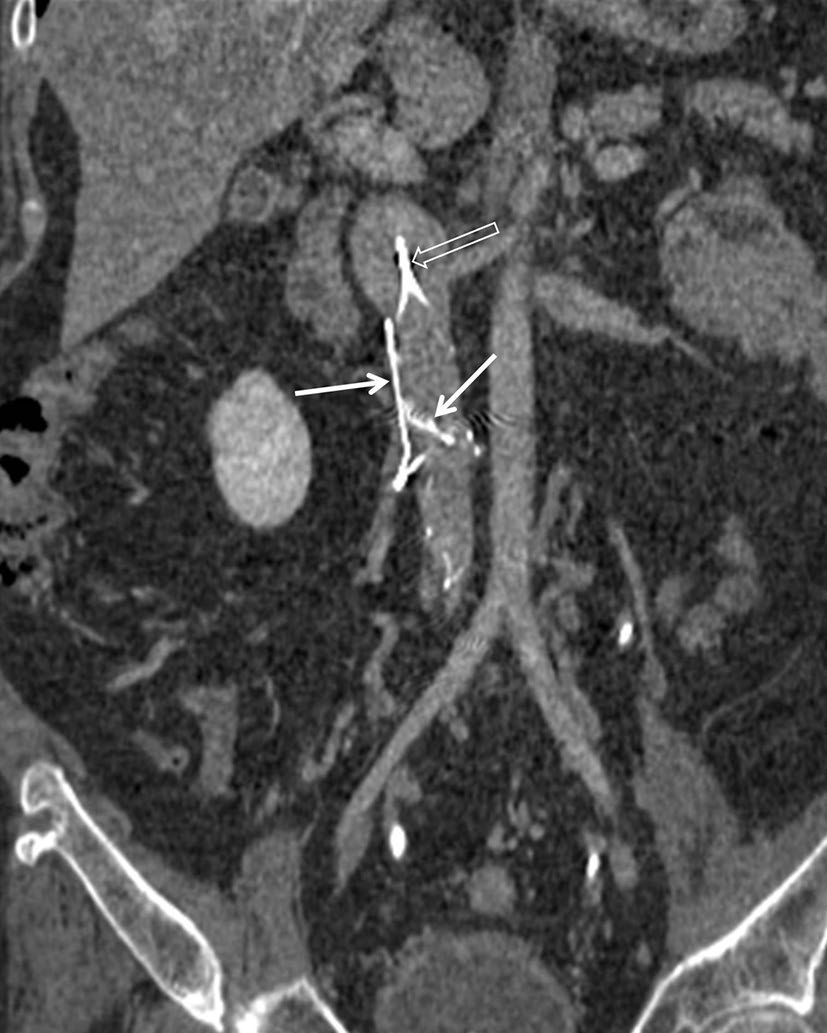

某些医疗器械的断裂可能与器械材料、植入时间、器械所处的解剖结构以及任何相关操作有关。支架断裂的报道发生率偏低,可能是由于意识不足以及对事件检测困难所致。胆道或胃肠道支架的断裂可能自发发生,也可能由用于治疗肿瘤再生的球囊扩张或氩等离子凝固引起(图16)[10]。这些断裂可能导致胃肠道出血、复发性胆道梗阻、肠梗阻或穿孔。

下腔静脉滤器已用于预防接受难治性抗凝治疗的患者发生危及生命的肺栓塞(图17)[1]。过滤器骨折的风险可能与过滤器在体内留置时间的长短有关,尽管报道的发生率约为5.5%;一项研究显示,在5.5年时的预测断裂率为40%(图18)[9]。此外,断裂碎片的迁移可导致危及生命的并发症。因此,如果不再需要防止肺栓子,应尽早考虑取出过滤器。